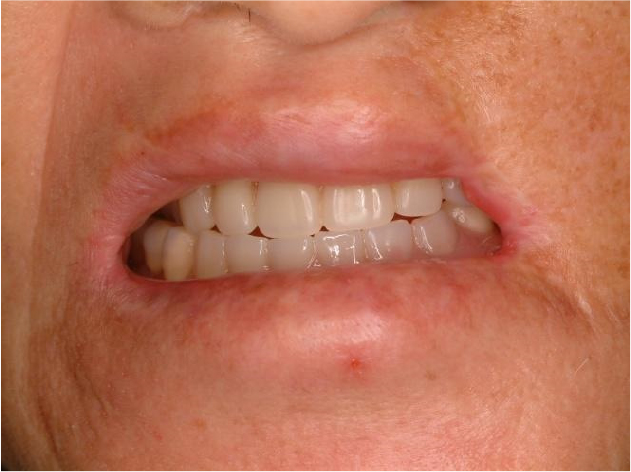

Postoperatively, the maximum mouth opening was increased from 12 to 35 mm, and the oral commissure was enlarged. After 2 months of recovery, temporary complete upper and lower dentures were delivered to the patient (Fig. 6). On January 19, 2011, two implants were placed in each arch under general anesthesia (Fig. 7). A panoramic radiograph revealed four implants (Fig. 8). At the Department of Prosthodontics, magnet-attached overdentures were fabricated and delivered 6 months after implant installation (Fig. 9). Vestibuloplasty creates a larger surface area for better denture adaptation. The patient was followed-up for 11 years without any complications (Fig. 10).